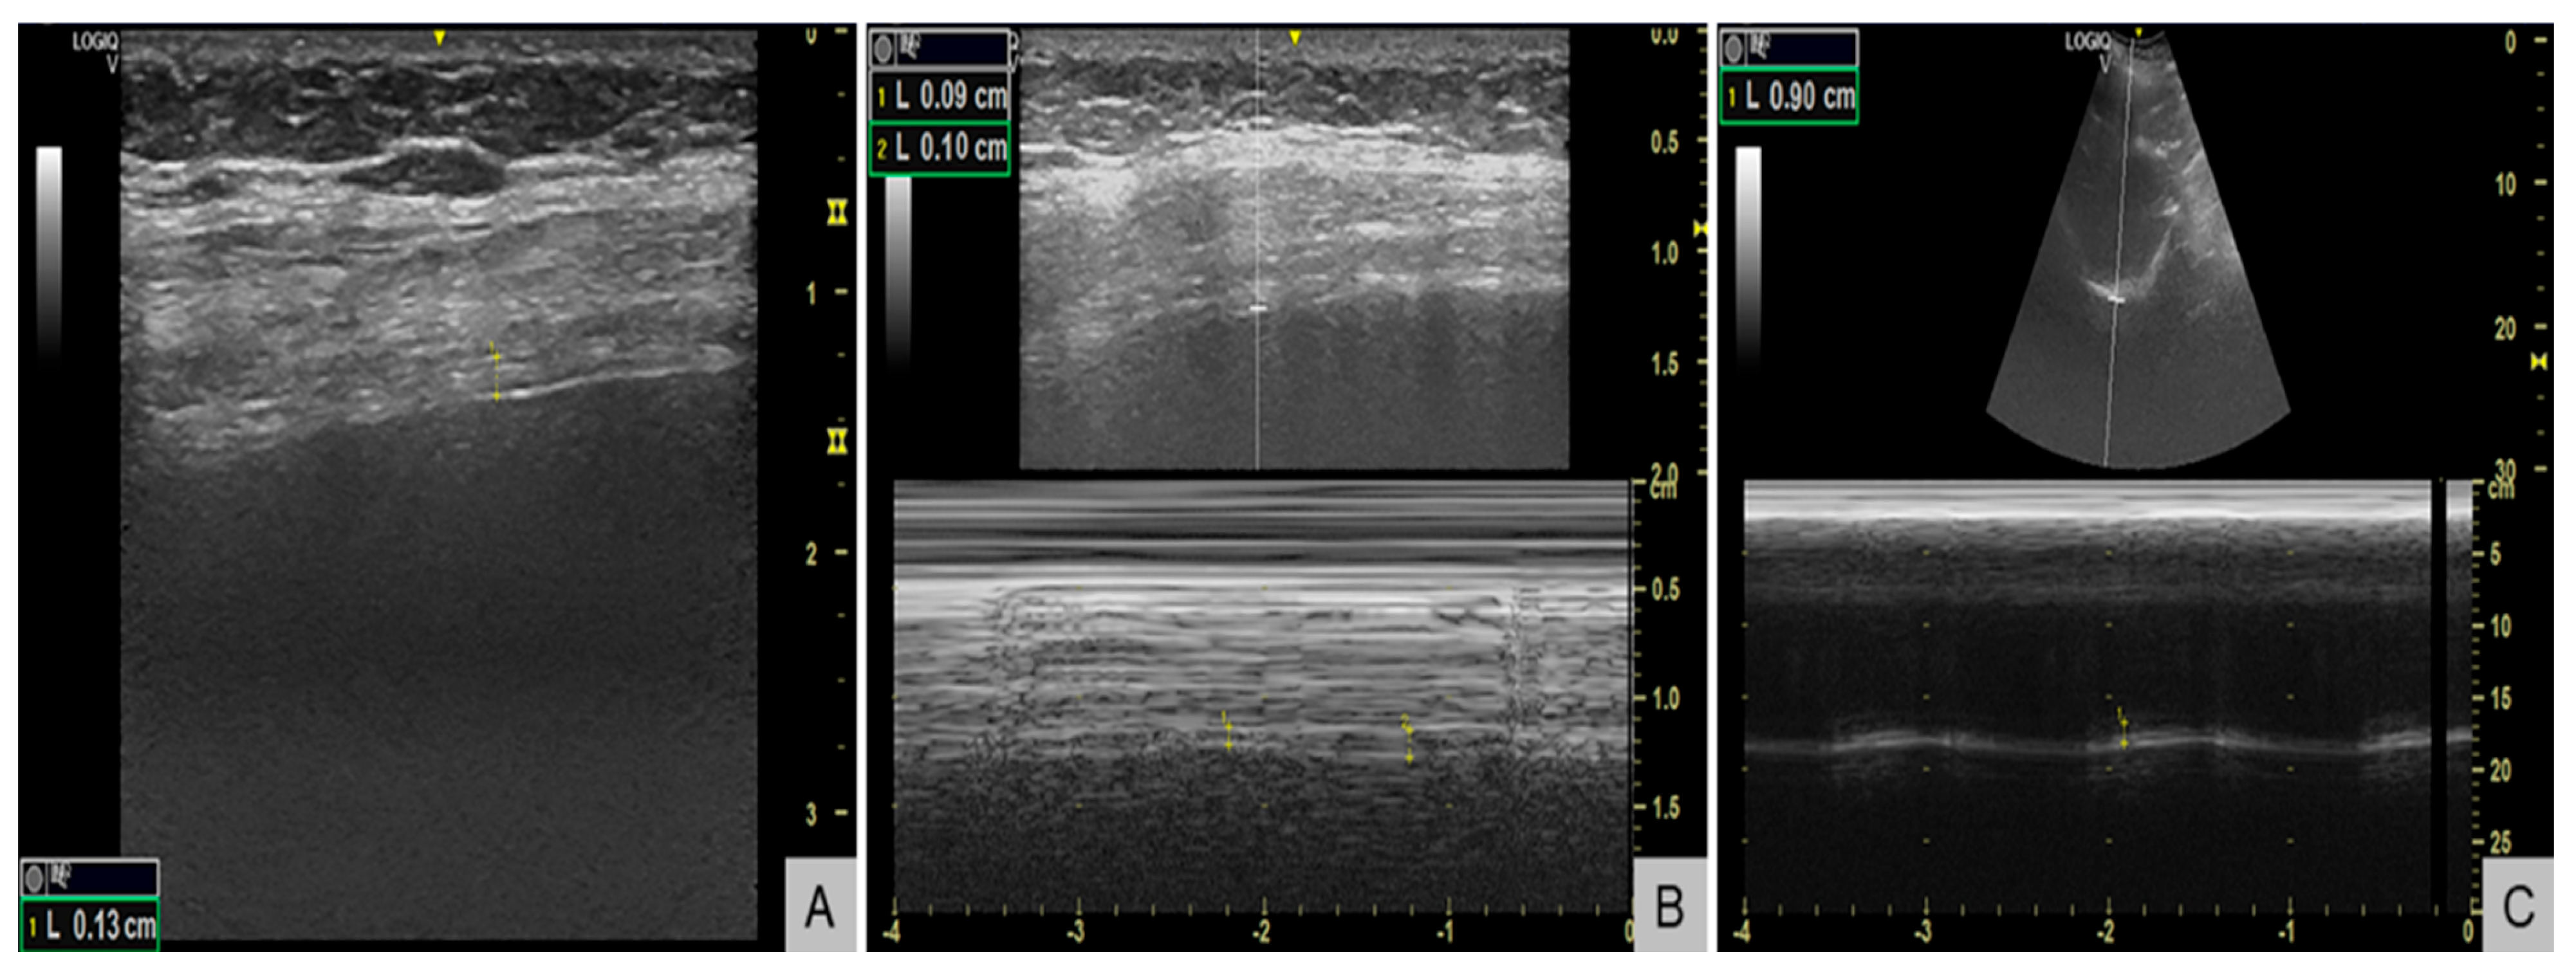

Respiratory evaluation also identified significant respiratory muscle weakness. Maximal inspiratory pressure (MIP) was −38 cmH2O (normal <−80 cmH2O in women), maximal expiratory pressure (MEP) +55 cmH2O (normal >100 cmH2O), and sniff nasal inspiratory pressure (SNIP) 34 cmH2O (normal >70 cmH2O), all below the lower limits of normal. Diaphragm ultrasound (Figure 3) revealed end-expiratory thickness 0.9 mm (right) and 1.3 mm (left) (normal for women >1.7–2.0 mm) (Figure 3A), thickening fraction 11% (right) (Figure 3B) and 16% (left) (normal >20%), and inspiratory excursion < 1.0 cm (Figure 3C) bilaterally (normal for women >1.5 cm during quiet breathing), consistent with diaphragmatic weakness. Polysomnography showed an apnea–hypopnea index of 13 events/hour, predominantly central hypopneas (n = 12), with a nadir oxygen saturation of 86% and no obstructive events. The patient’s body mass index was 23 kg/m2.

Figure 3.

Diaphragm ultrasound demonstrating diaphragmatic weakness. (A) B-mode image showing reduced end-expiratory diaphragm thickness of 1.3 mm in the left hemidiaphragm (normal for women >1.7-2.0 mm). (B) M-mode image showing a reduced thickening fraction of 11% in the right hemidiaphragm (normal >20%). (C) M-mode tracing showing reduced inspiratory excursion of 0.9 cm (normal for women >1.5 cm during quiet breathing).